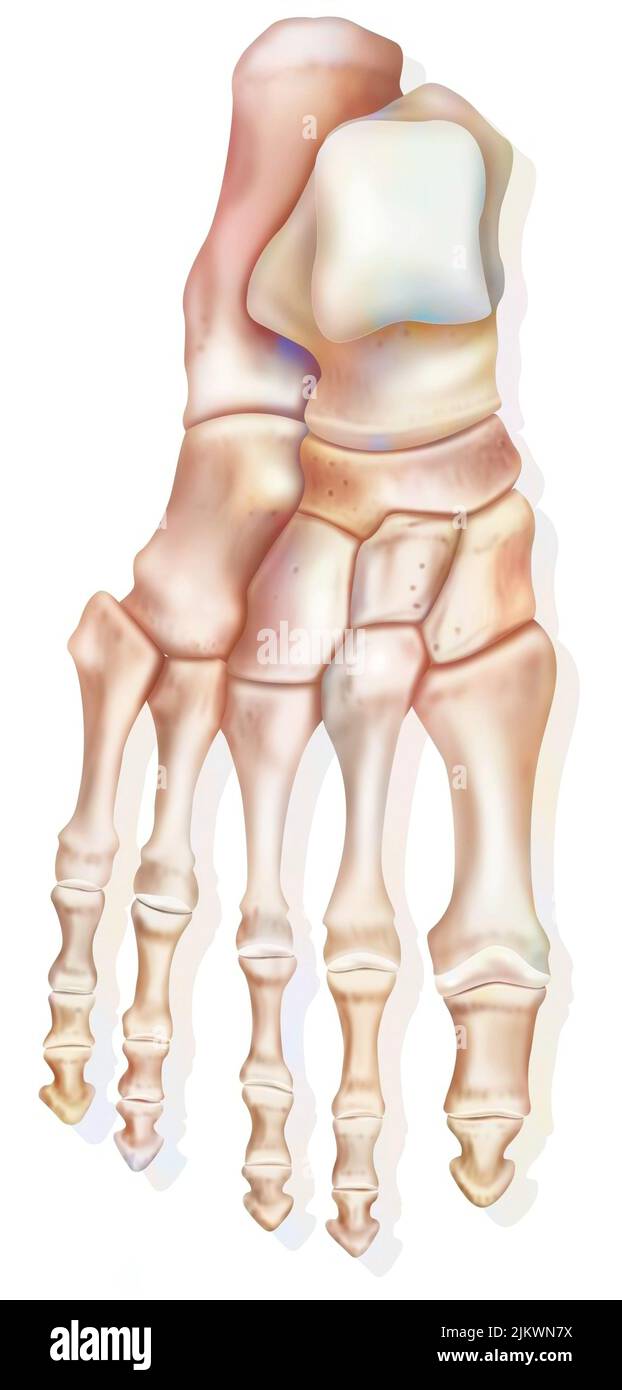

RF2K3D0JR–OS précis des os du pied gauche humain ou squelette 3D illustration du rendu. Vues latérales, médiales, dorsales et plantaires. Anatomie, ostéologie, squelette

RF2DHMD0H–OS du pied. Anatomie humaine. Le schéma montre l'emplacement et le nom de tous les os du pied.

RF2JKN2D2–OS de la cheville humaine, position correcte os de la cheville humaine. Illustration Anatomy Health Care.

RF2BTGDWM–Les os de la Tarsal du pied sont situés dans le milieu du pied et les zones de l'arrière du pied humain, dessin de ligne vintage ou illustration de gravure.